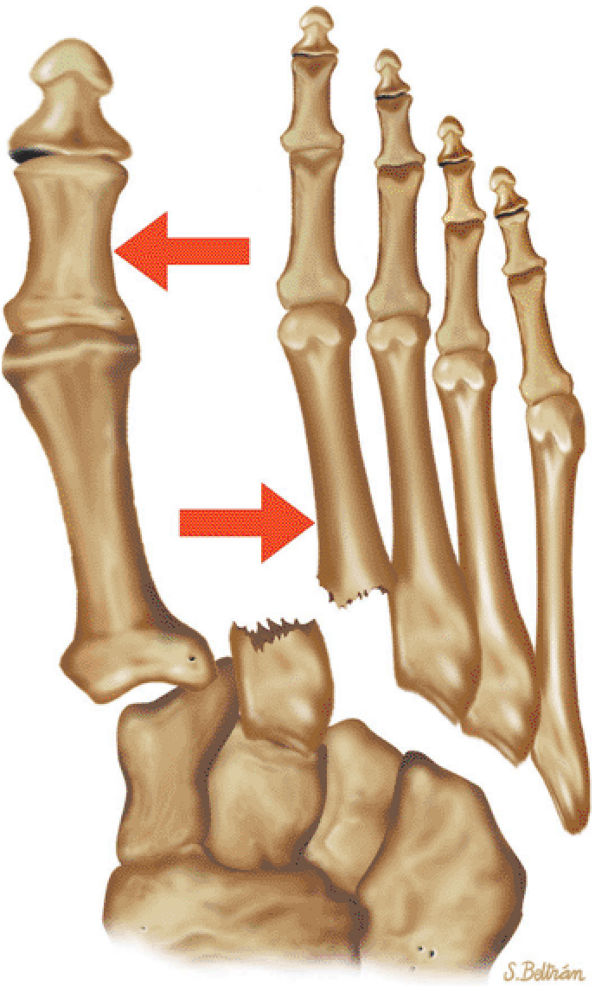

arthrosis at the tarsal-metatarsal joints in particular should prompt a careful search for Lisfranc fracture—dislocations in the axial plane.